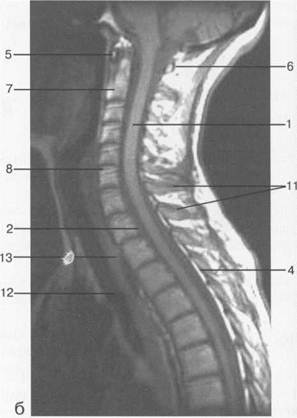

Рис. 3.14. МРТ. Срединное сагиттальное изображение шейного отдела позвоночника.

1 — спинной мозг; 2 — субарахноидальное пространство; 3 — дуральный мешок (задняя стенка); 4 — эпидуральное пространство; 5 — передняя дуга С1; 6 — задняя дуга С1; 7 — тело С2; 8 — межпозвонковый диск; 9 — гиалиновая пластинка; 10 — артефакт изображения; 11 — остистые отростки позвонков; 12 — трахея; 13 — пищевод.